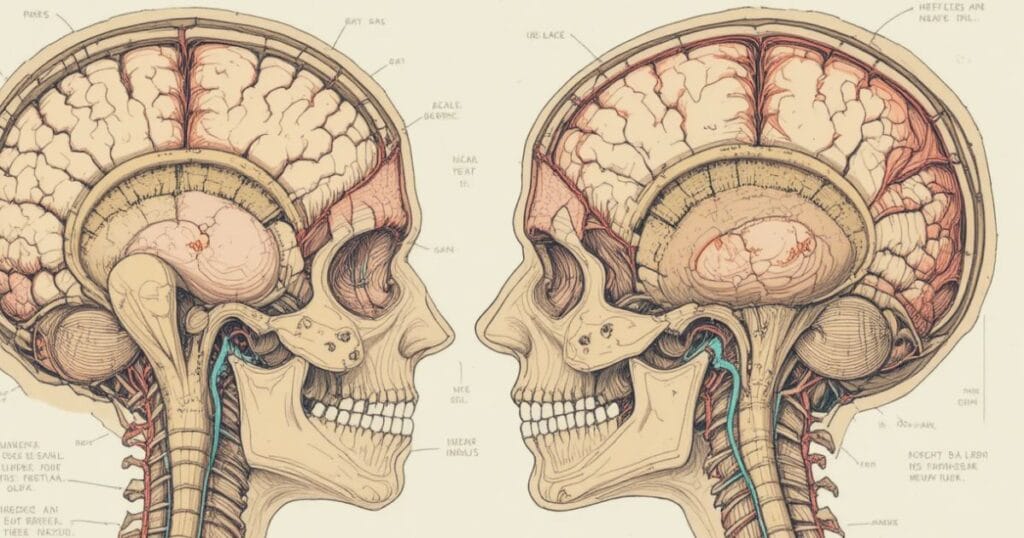

Head trauma refers to any injury that affects the scalp, skull, or brain. These injuries are typically divided into two main types—open brain injury and closed head injury.

An open brain injury happens when an object penetrates the skull, while a closed head injury results from internal pressure or force without breaking the skull. Both can damage the frontal lobe, causing behavioral or cognitive difficulties that change a person’s life completely.